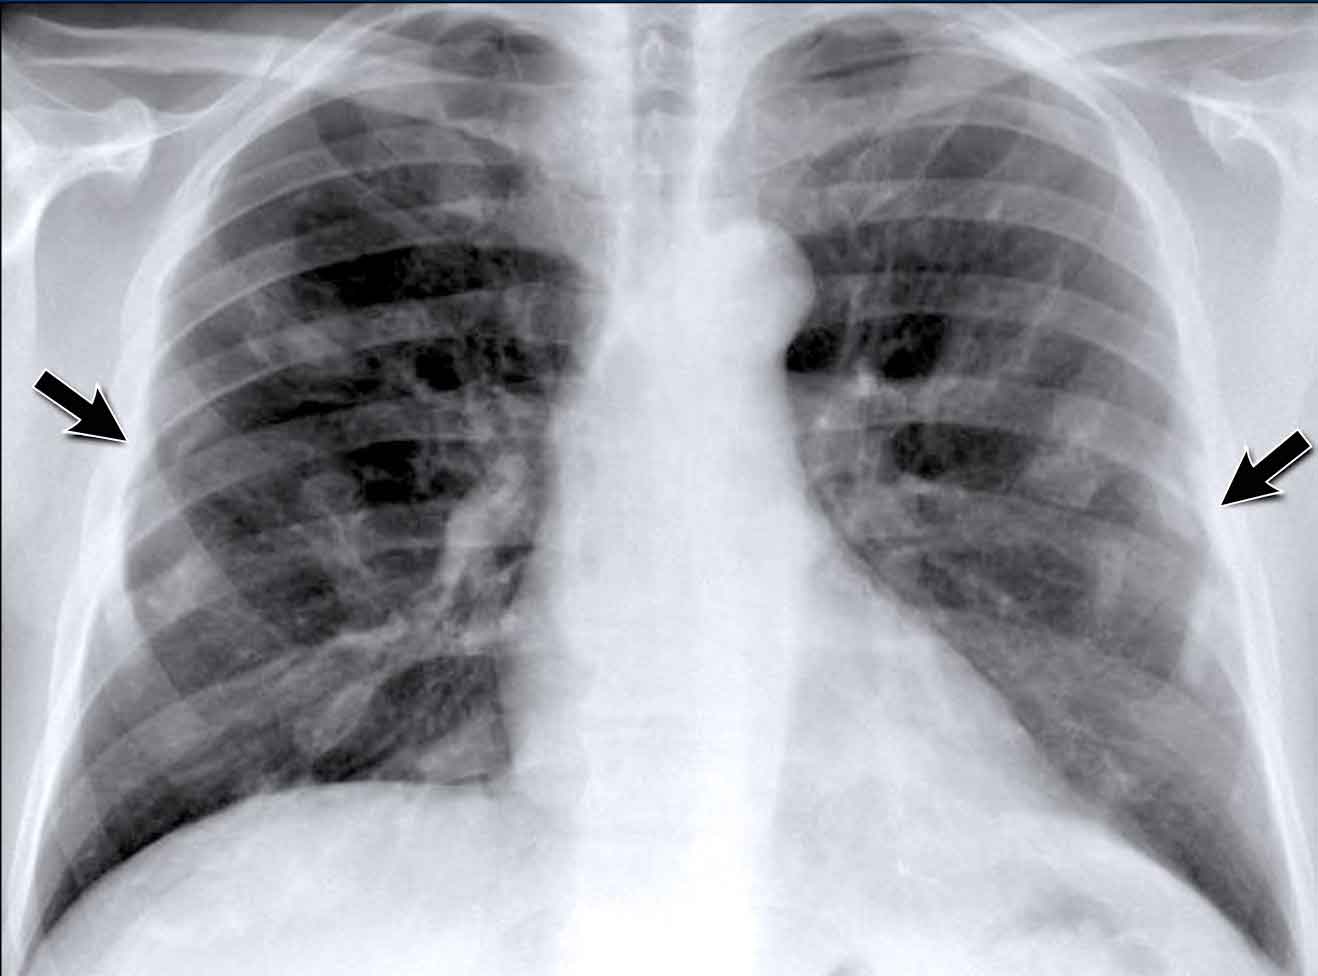

Hilar enlargement - case 1

In this case there is an enlarged hilar shadow on both sides.

This could be the result of enlarged vessels or enlarged lymph nodes.

A very helpful finding in this case is the mass on the right of the trachea.

This is known as the 1-2-3 sign in sarcoidosis, i.e. enlargement of left hilum, right hilum and paratracheal.

Here some more examples of sarcoidosis.

Click image to enlarge.

1. Lymphadenopathy and groundglass appearance of the lungs

2. Lymphadenopathy, 1-2-3 sign

3. Bulky lymphadenopathy

4. 1-2-3 sign

5. Nodular lung pattern, no lymphadenopathy

6. Hilar and paratracheal lymphadenopathy